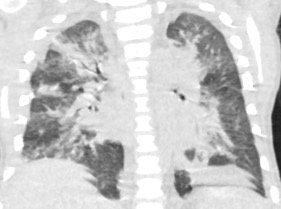

2951. Пациенту 5 лет с диагнозом «первичный гемофагоцитарный лимфогистиоцитоз» проведена аллогенная трансплантация гемопоэтических стволовых клеток, выполнена компьютерная томография, рентгенологическая картина соответствует _____ с гидротораксом и гидроперикардом